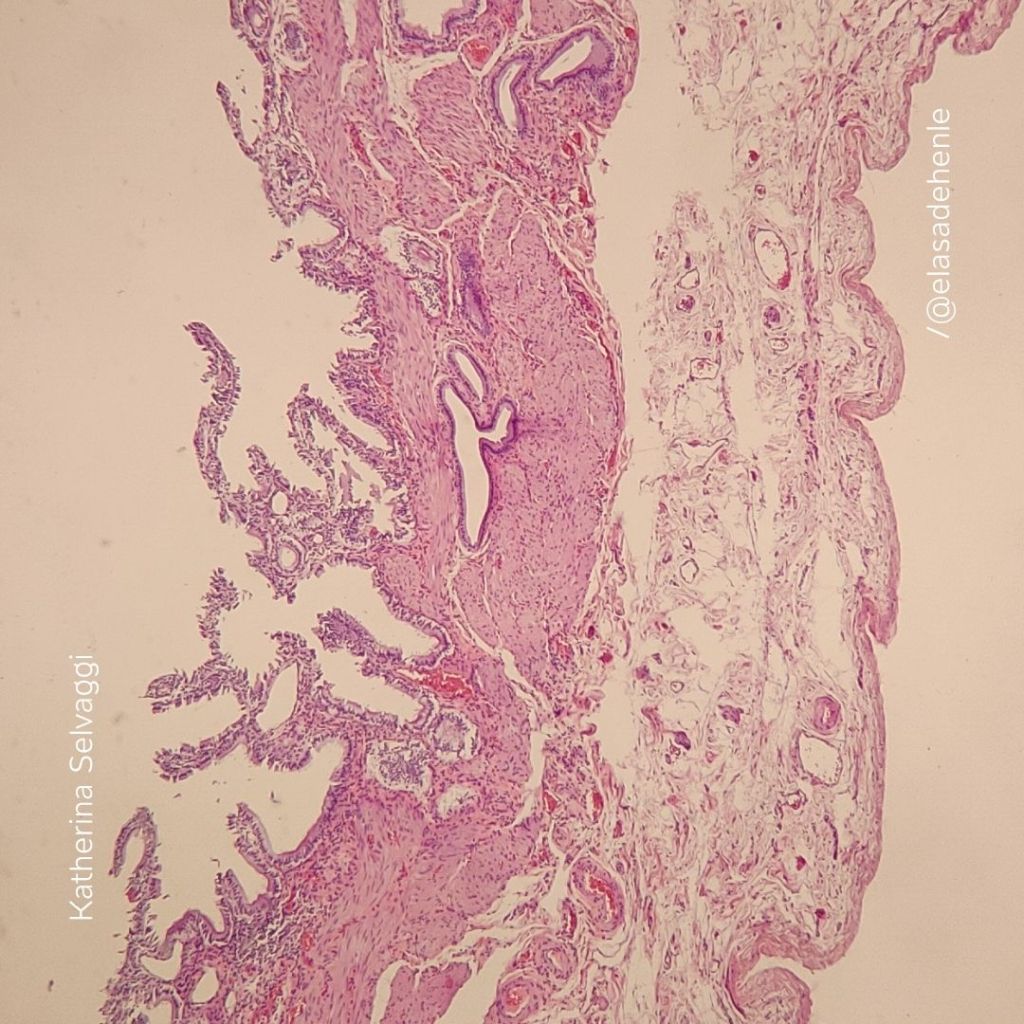

Corte en parafina

Vesícula biliar

COMECA